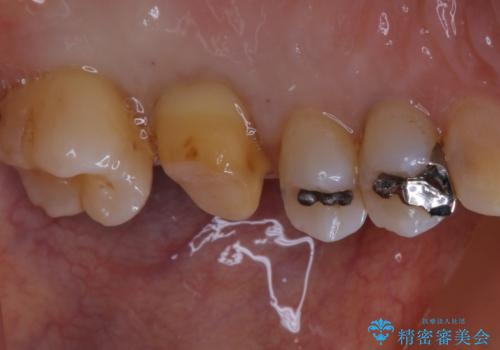

大きな詰め物を被せ物に変えて、歯の破折リスクを減らす

- 以前に異なる種類の材料で継ぎ接ぎ状態で修復されており、隙間のところから虫歯が再発していました。歯の手前側と後方及び内側に亀裂も入っていたため、将来的な虫歯再発のリスク及び歯の破折リスクを最小限にとどめるよう、被せものにて治療を行いました。